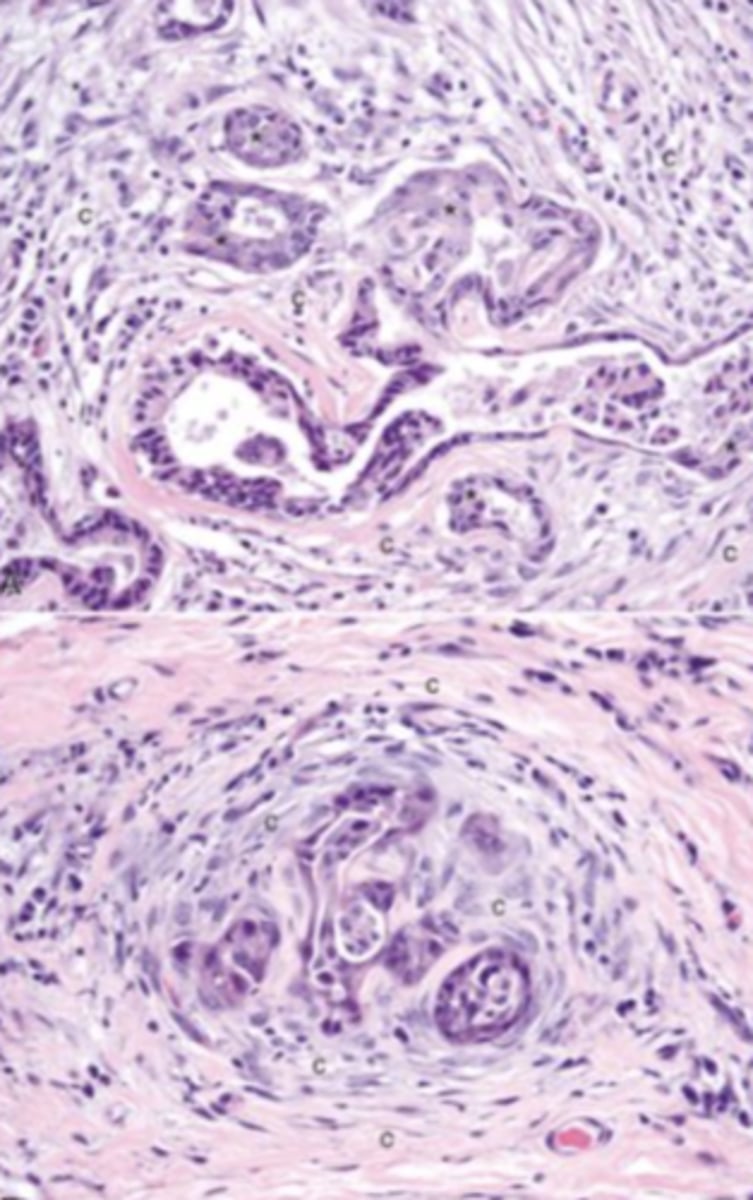

Cholangiocarcinoma

-tumor of the bile ducts

What has caused this gross appearance of this liver?

Cholangiohepatitis

-inflammation of the biliary ducts and parenchyma

-expanded bile ducts

What has caused this histologic appearance of this liver?

adenocarcinoma

-malignant tumor of epithelial origin

-tubular patterns on histopath

What kind of tumor is this?

schirrous response

What type of response is produced by this carcinoma?